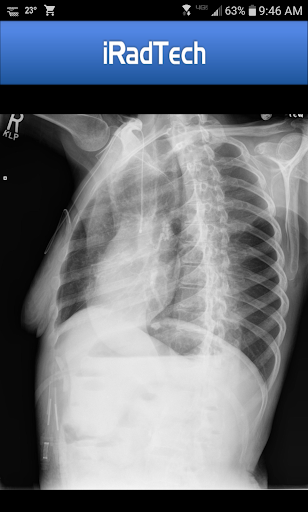

Here’s what you do: there’s detailed instructions for over 200 different x-ray positions. It’s got stuff like technical factors, patient positioning, image quality tips, and all that. And there’s also representative radiographic images you can zoom in on, which is pretty useful. And it even gives you suggested digital imaging settings for each position – super handy.